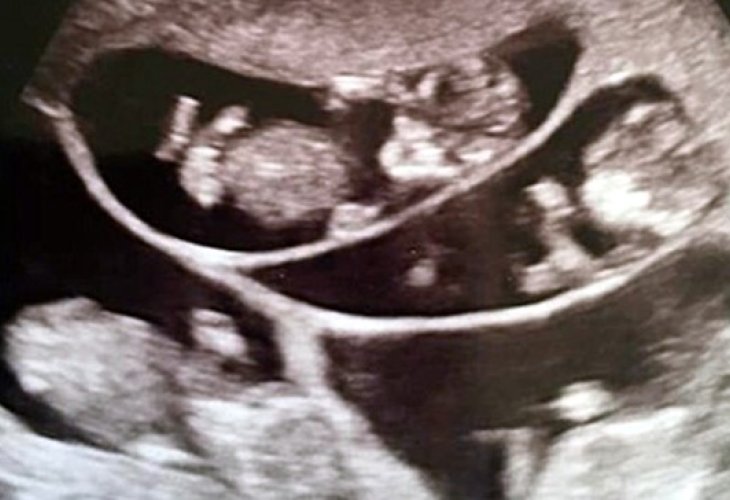

But then, when Courtney came for one of the late-stage pregnancy ultrasound checks, the doctors looked at the screen and couldn't believe their eyes. "It took them a moment or two to process what they were seeing," the couple smiles and says. "Then they told us we were going to be the parents of no less than six children."